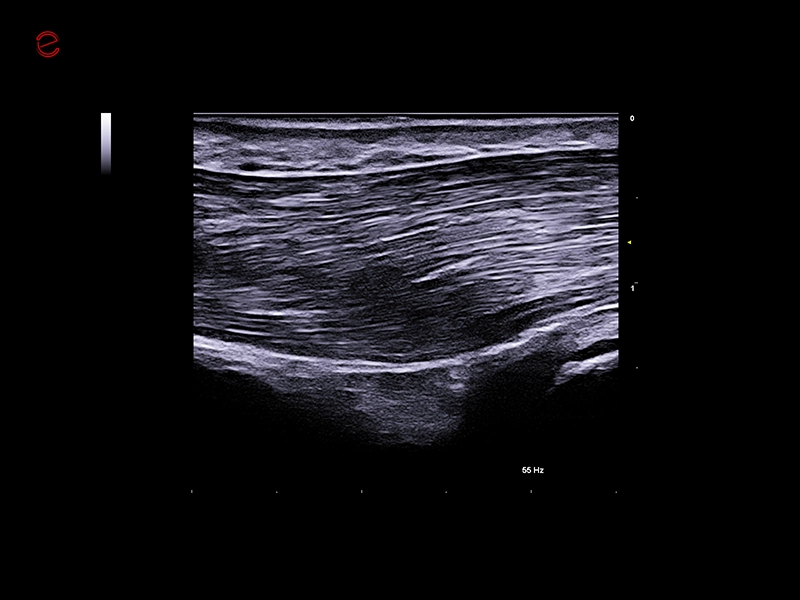

MyLab™9 Platform - Very-superficial linear imaging with Power Doppler algorithm

MyLab™9 Platform - Very-superficial linear imaging with Power Doppler algorithm